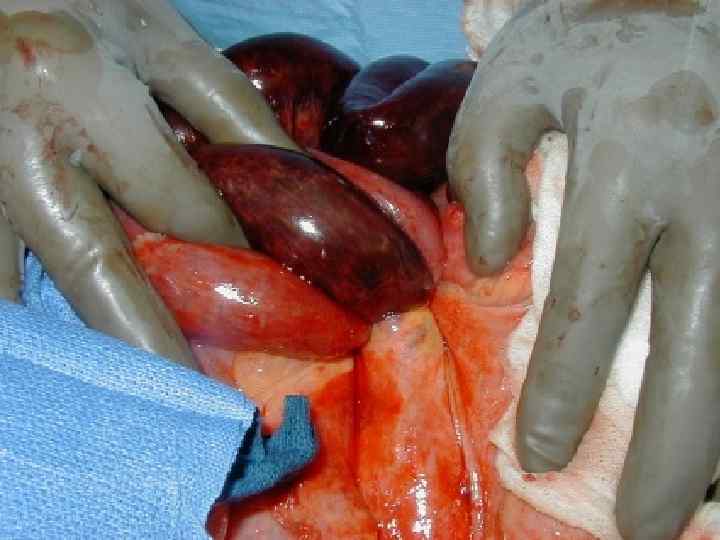

ПРИЗНАКИ НЕЖИЗНЕСПОСОБНОСТИ КИШКИ • окраска – багровый или черный цвет • отсутствие пульсации краевых сосудов брыжейки • отсутствие перистальтики

ОСЛОЖНЕНИЯ УЩЕМЛЕННОЙ ГРЫЖИ • Флегмона грыжевого мешка • Острая странгуляционная кишечная непроходимость